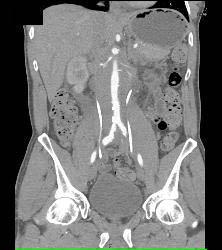

Retroperitoneal Fibrosis Displaces the Ureters